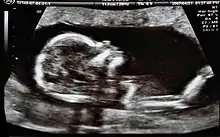

Ecografía fetal

Se utiliza para producir imágenes del feto mientras está en el útero para evaluar el crecimiento y desarrollo del bebé, y monitorear el embarazo. Por medio de esta prueba se pueden identificar muchas condiciones que pueden ser peligrosas tanto para la madre como para el hijo. Se utiliza para:[18]

- confirmar el embarazo y la ubicación (algunos fetos se desarrollan fuera del útero)

- determinar la edad de gestación del bebé

- confirmar la cantidad de bebés

- evaluar el crecimiento del bebé

- estudiar la placenta y los niveles de líquido amniótico

- identificar defectos congénitos

- investigar complicaciones

- realizar otros estudios prenatales

- determinar la posición del feto antes del parto.